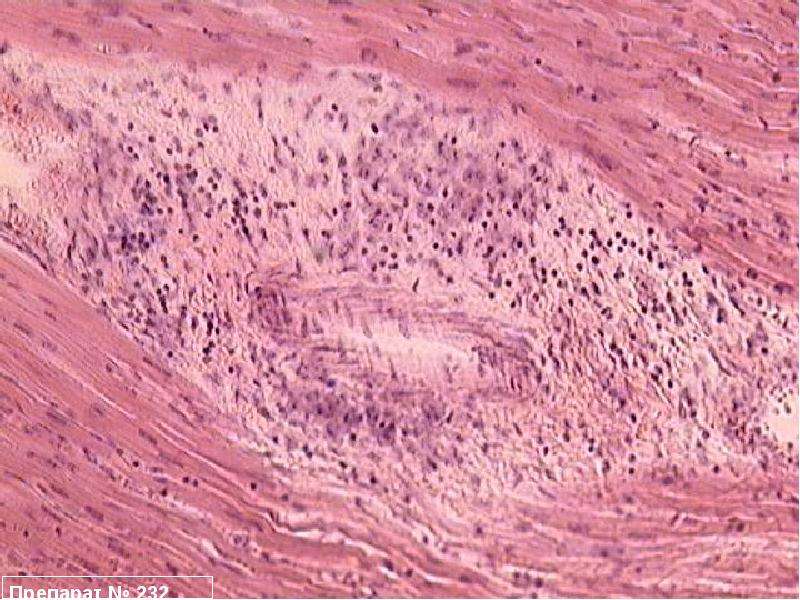

Межуточный миокардит: гистологические исследования